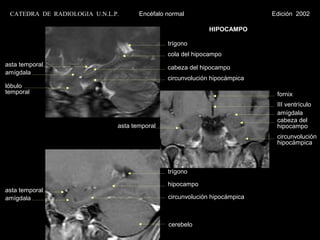

HIPOCAMPO

trígono

cola del hipocampo

asta temporal                                 cabeza del hipocampo

amígdala

circunvolución hipocámpica

lóbulo

temporal                                                                    fornix

III ventrículo

cabeza del

asta temporal                                 hipocampo

circunvolución

hipocámpica

asta temporal

amígdala                                      circunvolución hipocámpica

cerebelo